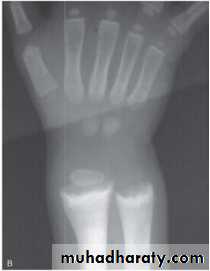

Rachitic changes are most easily visualized on posteroanterior radiographs of the wrist,

Decreased calcificationthickening of the growth plate.

fraying: The edge of the metaphysis loses its sharp border.

cupping: the edge of the metaphysis changes from a convex or flat surface to a more concave surface. most easily seen at distal ends of the radius, ulna, fibula.

widening of the distal end of the metaphysis, corresponding to the clinical observation of thickened wrists and ankles, as well as the rachitic rosary.

Coarse trabeculation of the diaphysis and generalized rarefaction.

Most cases of rickets are diagnosed based on the classic radiographic abnormalities